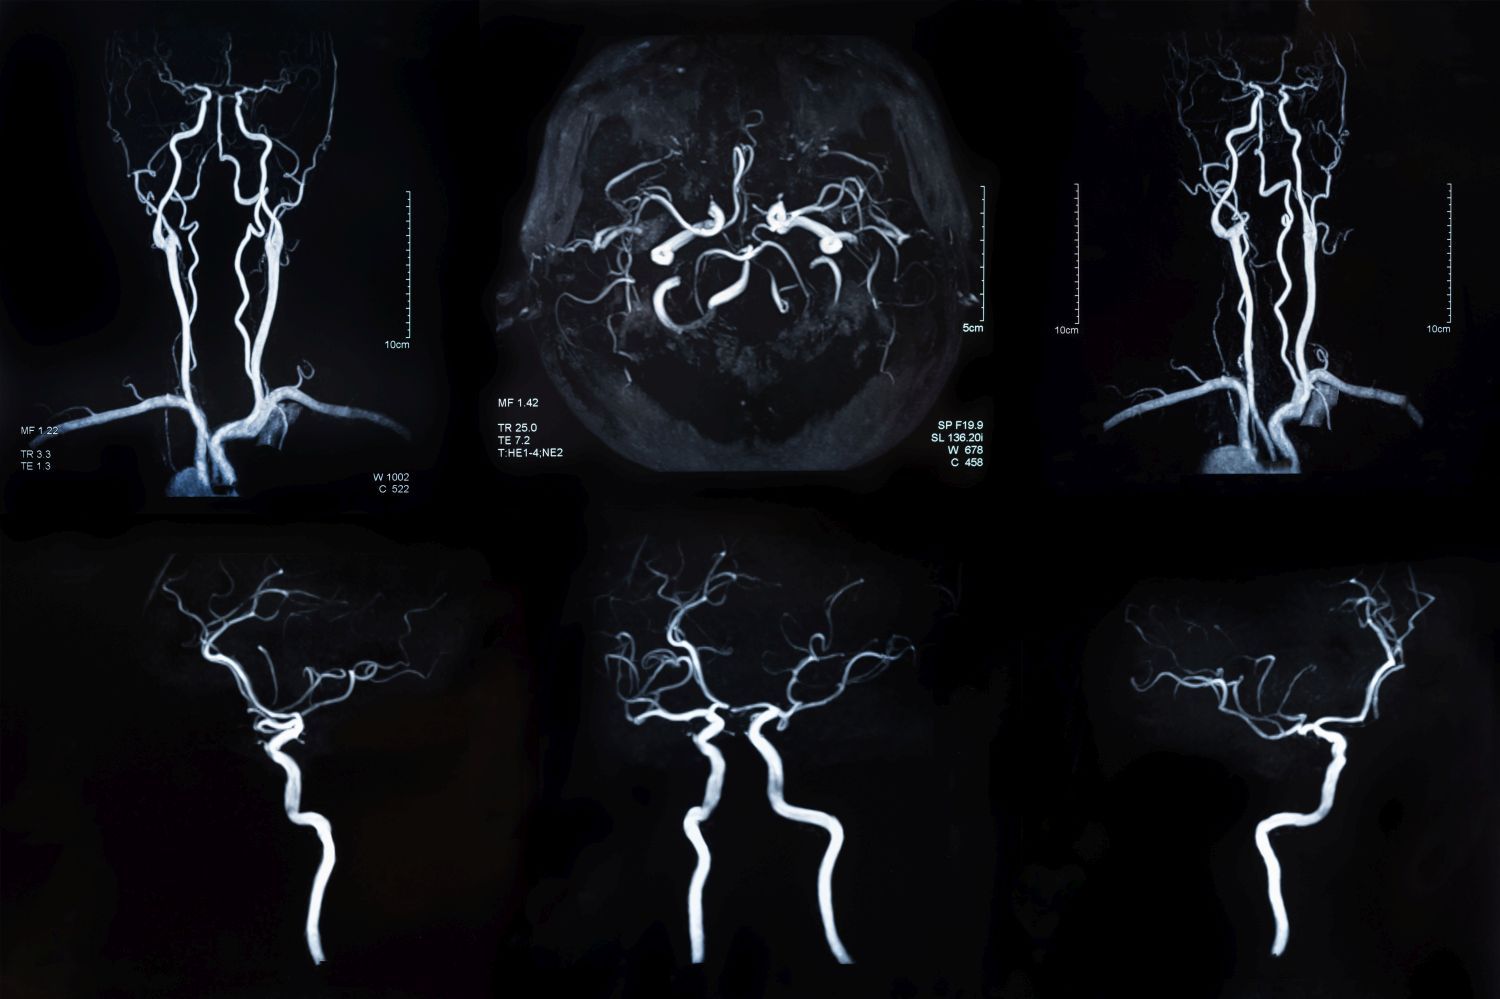

An aneurysm is initially small, grows slowly, causes no symptoms and therefore goes unnoticed for a long time. The bulge in the vascular wall of a blood vessel acts like a small balloon. If this loses much of its elasticity over time and expands too much, the aneurysm can eventually rupture, causing bleeding inside the body – a life-threatening condition that requires emergency surgery.

Aneurysms most frequently form on the aorta, the main artery in the abdomen or chest. “4-8 percent of men over 65 and 0.5-1.5 percent of women over 65 have an aortic aneurysm of at least three centimetres in diameter,” explains Alexander Zimmermann, Director of the Clinic for Vascular Surgery. Brain aneurysms, the second most common form, occur in 2-3 percent of the population.

Apart from a few congenital aneurysms, most develop in the course of life. “One factor here is the normal ageing process, as blood vessels automatically become less elastic with age,” explains Zsolt Kulcsár, Clinic Director of Neuroradiology. If other factors that are harmful to the cardiovascular system such as smoking, high blood pressure, obesity or high blood lipid levels are added to this, the risk of developing an aneurysm increases. “Controlling vascular risk factors is therefore an important measure to prevent serious consequential damage,” emphasizes Luca Regli, Clinic Director of Neurosurgery.

Because aneurysms usually do not cause any symptoms, they are often discovered by chance during an examination. At the USZ, they are then assessed and treated on an interdisciplinary basis. Special imaging techniques and other tests are used to analyze the size and composition of the tumor. “With the majority of aneurysms, there is no acute danger. They just need to be checked regularly,” explains Alexander Zimmermann. Regular follow-up checks allow growing aneurysms to be detected early and, if necessary, treated more safely. “We also provide advice on lifestyle changes. This has an influence on how an aneurysm develops,” adds Zsolt Kulcsár.